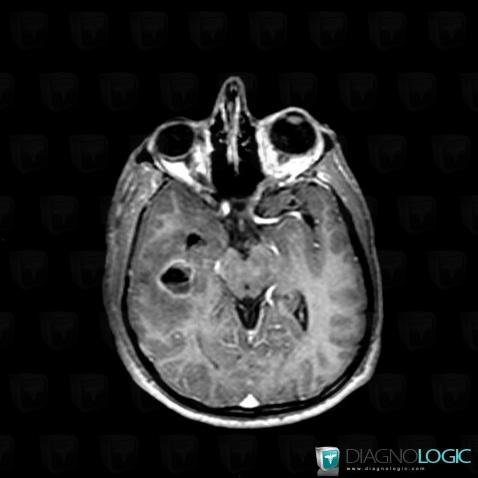

Abscess, Cerebral hemispheres, MRI

Here is the specific information in the key image above:

- Diagnosis Abscess, Location(s) Cerebral hemispheres, with gamuts Intracerebral lesion with ring enhancement, Intracerebral lesion with moderate enhancement